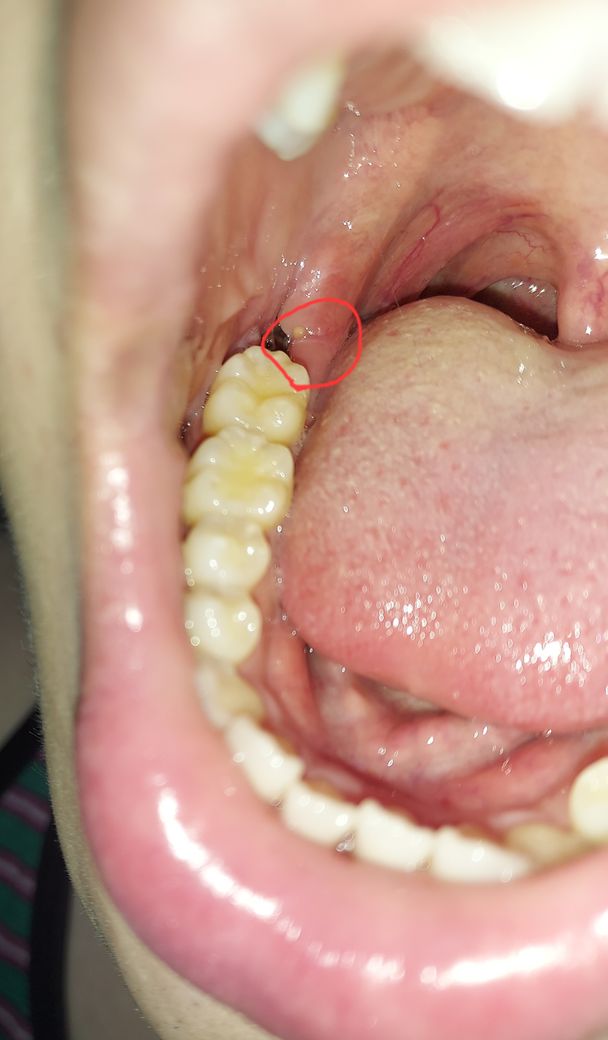

사랑니 발치 후 잇몸 농양? 좁쌀? 발생

안녕하세요 2주 전에 사랑니를 뺐는데요 7일 후 실밥을 뽑으러 가니 실밥이 파묻혀 못찾겠다고 마취를 한 뒤 1시간동안 잇몸을 헤집어 다시 피가 났습니다.

그러고 말하기를 자기는 실밥을 최대한 뽑았는데 혹시 남아있다면 염증이 날 수도 있다고 했습니다.

그 후로 6일이 지났는데 근처에 좁쌀같은 농양이 발생하였습니다.

가만히 놔둬야하나요 치과를 다시 가야하나요??ㅜㅜ

• 1번 째 사진

사진상으로는 크게 문제가 있어 보이진 않습니다. 음식물만 남자 않도록 식사를 하시고 나서 물로 여러번 헹궈주시면될것같습니다.

1. 사진이 있다면 좀 더 도움되는 답변을 드릴 수 있을 것 같습니다. 치과에 가서 다시 상태를 보는 것이 좋을 것 같습니다.

2. 감염으로 인해 생긴것이거나 남아있는 봉합실 이물질 때문에 나타나는 반응일 수 있습니다.

3. 감염이라면 치과에서는 세척 및 항생제 처방을 해줄 것이며 봉합실이 남아있는지 다시 한번 체크해보면 좋을 것 같습니다.